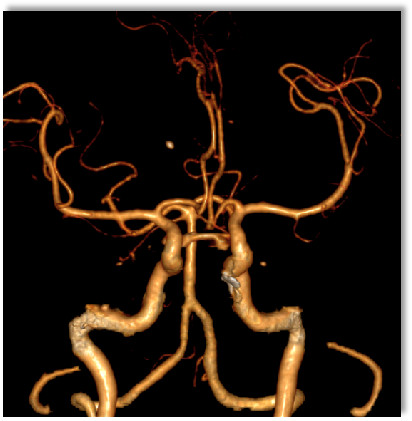

CTA